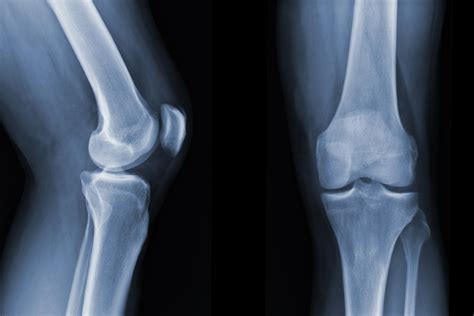

What Does a Normal Knee Xray Look Like?

A radiologist interprets a knee X-ray by looking at several key anatomical landmarks. When a report comes back as a normal knee xray, it means the technician and radiologist have observed the following components as being within standard clinical limits:

• Bone Integrity: There are no visible breaks, hairline fractures, or bony abnormalities.

• Joint Space: The gap between the femur (thigh bone) and the tibia (shin bone) is symmetrical and maintained, which suggests that the articular cartilage has not significantly eroded.

• Alignment: The bones are in their proper anatomical position, indicating there are no major dislocations or congenital malalignments.

• Soft Tissue Shadows: While X-rays are primarily for bones, they can sometimes show swelling or fluid accumulation (effusion) around the knee joint.

Because X-rays primarily capture dense tissue, a "normal" result confirms that the structural framework of your knee is intact. This is excellent news if you were concerned about a broken bone or severe bone deformity.